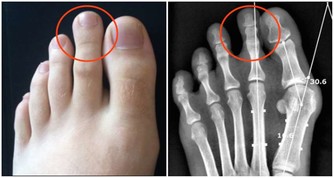

6 地西泮:易有依賴性,半夜起夜要小心

地西泮又被稱之為“安定”,有鎮靜、催眠的作用,有的老人半夜起夜,而這個時候藥品藥效還存在,因而起床後會有頭暈表現,在這種迷糊的狀態下老人容易摔倒,甚至導致骨折,因而靠催眠藥治失眠的老人,起床時要特別小心。